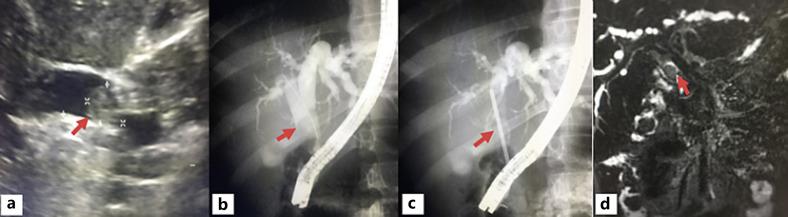

Carcinoma of the extrahepatic biliary tract accounts for <2% of all cancers. Neuroendocrine tumor of the extrahepatic bile duct is very rare, and there are <200 cases reported since 1959. The preoperative diagnosis is infrequent (5.12%). The definite diagnosis relies on postoperative pathology which utilized immunohistochemistry study on many biomarkers to diagnose the histological subtypes of neuroendocrine neoplasms, such as chromogranin A, synaptophysin, and neuron-specific enolase. When the primary tumor has no metastases, radical removal of the lesion appears as curative treatment. The treatment of the carcinoid syndrome or other functioning syndrome is the first priority. We report a case of a 12-year-old Mexican woman with neuroendocrine tumor of the extrahepatic bile duct (common bile duct neuroendocrine tumor) seen in our hospital. Resection of the common bile duct, cholecystectomy, end to side Roux-en-y hepaticojejunostomy, and portal lymphadenectomy was performed. A review of the pertinent literature was performed. Given the rarity of the disease, treatment principles are based mainly on retrospective series and case reports. We present the eighth case in adolescence in the literature.

肝外胆道癌占所有癌症的比例不到2%。肝外胆管神经内分泌肿瘤非常罕见,自1959年以来报告的病例不到200例。术前诊断不常见(5.12%)。明确诊断依赖于术后病理,术后病理利用对多种生物标志物的免疫组化研究来诊断神经内分泌肿瘤的组织学亚型,如嗜铬粒蛋白A、突触素和神经元特异性烯醇化酶。当原发性肿瘤无转移时,根治性切除病变似乎是治愈性治疗。类癌综合征或其他功能性综合征的治疗是首要任务。我们报告了我院收治的一例12岁墨西哥女性肝外胆管神经内分泌肿瘤(胆总管神经内分泌肿瘤)病例。进行了胆总管切除、胆囊切除、端侧Roux-en-y肝空肠吻合术和门静脉淋巴结清扫术。对相关文献进行了回顾。鉴于该疾病的罕见性,治疗原则主要基于回顾性系列研究和病例报告。我们呈现了文献中青少年的第八例病例。